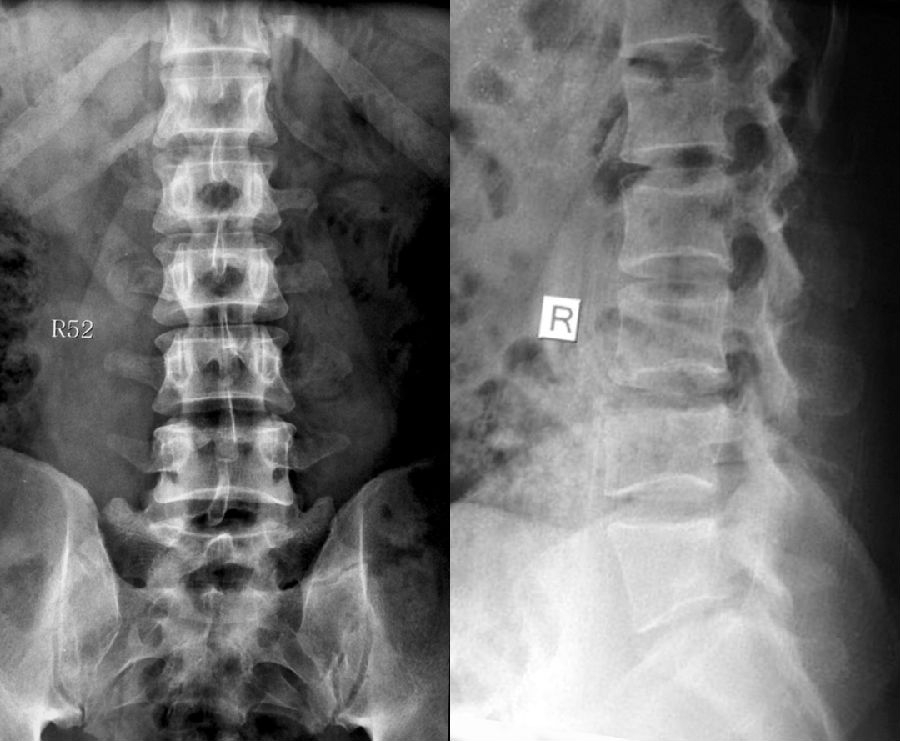

1984年,Castellvi提出LSTV分类系统将移行椎分为Ⅰ-Ⅳ型。

目前,腰骶移行椎以Castellvi的分类方法最为常用。其主要根据横突形态及其与骶骨、髂骨是否融合或形成假关节而分为4型,Ⅰ、Ⅱ、Ⅲ型又根据单、双侧分为A、B两个亚型。

正常

I型:主要为腰5横突发育不良,横突宽度大于19mm,并将其分为两个亚型Ia(单侧横突发育不良)或Ib(双侧横突发育不良)

L5右侧横突肥大,为Ⅰa型

L5双侧横突肥大,为Ⅰb型

II型:表现为不完全的腰椎骶化,具有增宽的横突,并且和骶骨形成假关节,并将其分为两个亚型IIa(单侧关节形成)或IIb(双侧关节形成)

L5左侧横突肥大,假关节形成,为Ⅱa型

L5双侧横突肥大,假关节形成,为Ⅱb型

III型:单侧(IIIa)或双侧(IIIb)腰椎完全骶化,腰5横突与骶骨完全骨性融合

L5右侧横突肥大与骶骨发生骨性融合,为Ⅲa型

L5双侧横突与骶骨骨性融合,为Ⅲb型

IV型:一侧为II型即腰5横突与骶骨形成假关节,对侧为III型即腰5横突与骶骨形成骨性融合

IV型即混合型:L5双侧横突肥大,一侧与骶骨相接触为Ⅱ型表现,另一侧与骶骨形成骨性融合为Ⅲ型